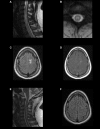

Antibodies against myelin oligodendrocyte glycoprotein (MOG-IgG) have been found in some cases diagnosed as seronegative neuromyelitis optica spectrum disorder (NMOSD). MOG-IgG allowed the identification of a subgroup with a clinical course distinct from that of NMOSD patients who are seropositive for aquaporin-4-IgG antibodies. MOG-IgG is associated with a wider clinical phenotype, not limited to NMOSD, with the majority of cases presenting with optic neuritis (ON), encephalitis with brain demyelinating lesions, and/or myelitis. Therefore, we propose the term MOG-IgG-associated Optic Neuritis, Encephalitis, and Myelitis (MONEM). Depending on the clinical characteristics, these patients may currently be diagnosed with NMOSD, acute disseminated encephalomyelitis, pediatric multiple sclerosis, transverse myelitis, or ON. With specific cell-based assays, MOG-IgG is emerging as a potential biomarker of inflammatory disorders of the central nervous system. We review the growing body of evidence on MONEM, focusing on its clinical aspects.